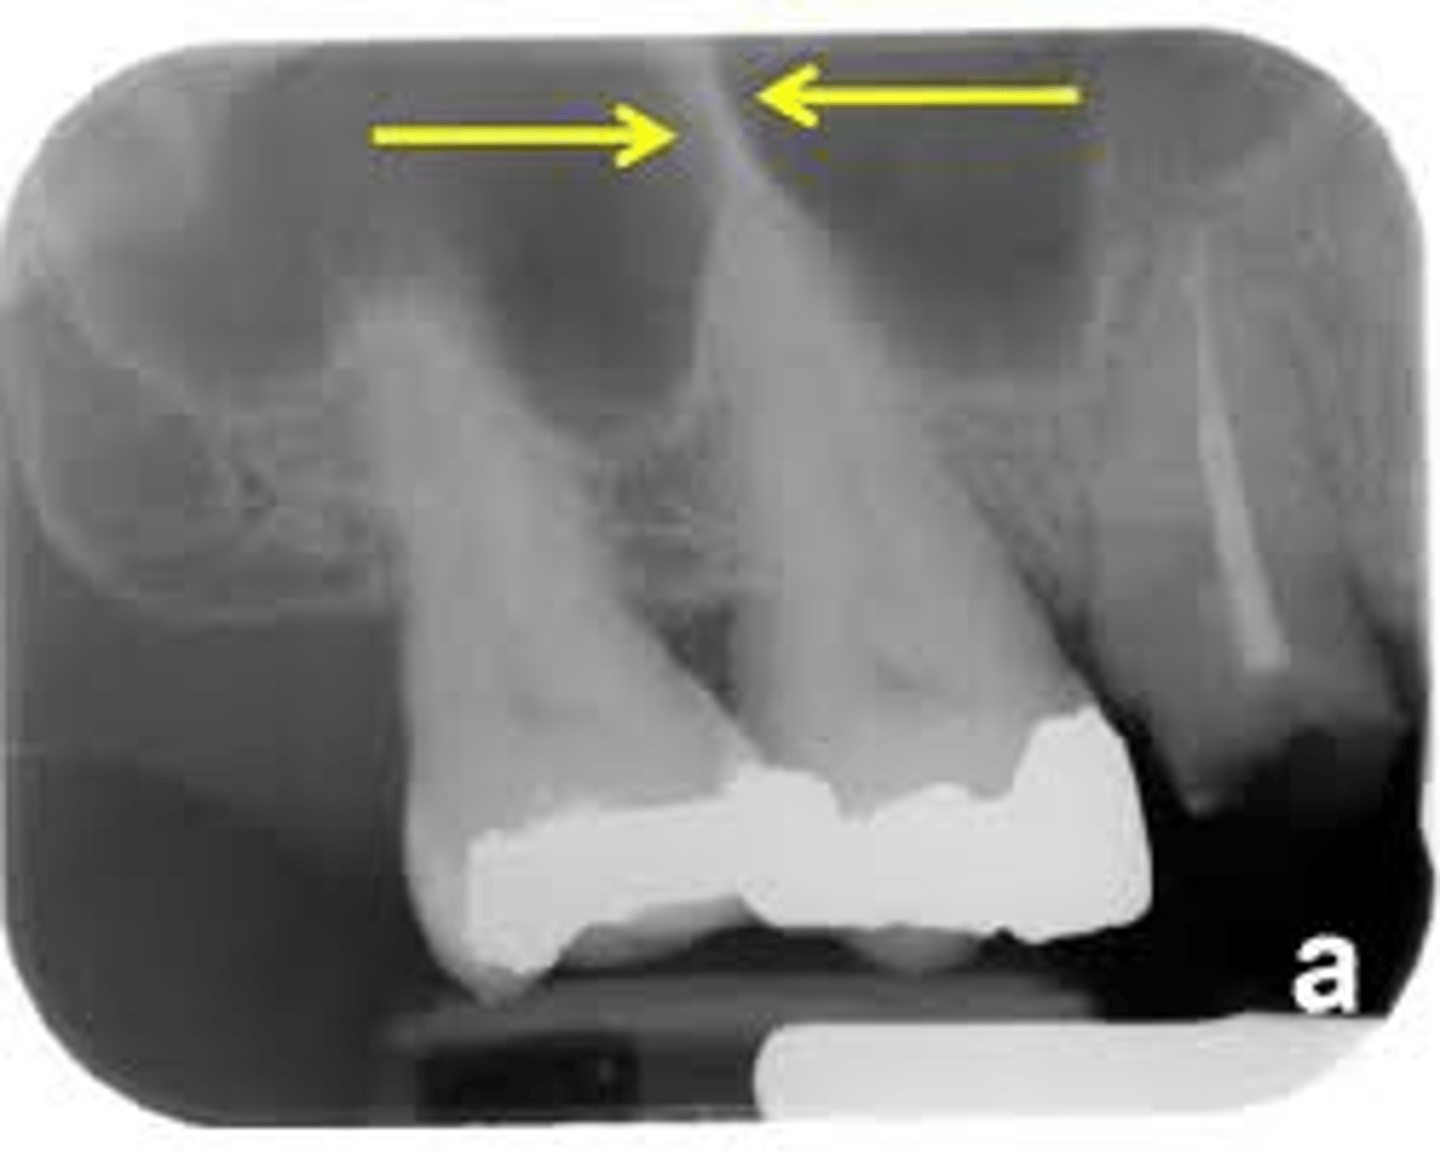

external oblique ridge

dense white line distal to the last molar and moving across root of molars

internal oblique ridge

located below the external oblique ridge

less dense

ridge of bone that extends across roots